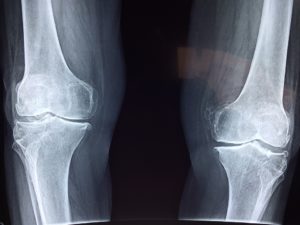

Inflammation response doesn’t always ‘turn off’ when the healing job is done, and sometimes it’s triggered throughout the body without any injury or infection to set it off. In that case, it’s called ‘chronic’ inflammation, which is the subject of increasing research. Findings show that chronic inflammation may contribute to rheumatoid arthritis, gout and many other joint problems and health issues.

Inflammation may speed aging and make people more vulnerable to disease. It happens so slowly that we hardly notice it (until we get sick), and it can really only be diagnosed by a blood test to identify a protein called cytokine, which is believed to be evidence of measurable chronic inflammation. This is a new field of research – but scientists do know that managing your inflammation with diet, exercise and supplements can help with joint health.